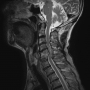

허리디스크수술직후 교통사고